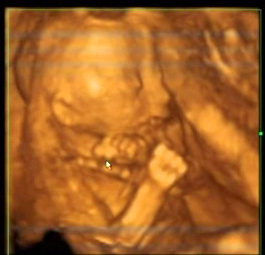

Zdravím všechny, jsem tu poprvé a ráda bych se přidala do Vaší konverzace. Mám termín 22.5., ale už pátý týden ležím s nohama nahoře, kvůli krátkému děložnímu čípku a CS4... :( Prý takhle budu ležet ještě dalších 8 týdnů. Co doktor, to jiný názor, tak už jsem z toho taky Matěj. Jedni tvrdí, že ležení zkracování čípku bůh ví jak neovlivní, druzí mi vyhrožují nemocnicí. Zatím držim a ležim, ale začíná mi z toho tak trochu hrabat. Zatím jsem přibrala 7kg, ale dneska jsem se nechutně přejedla, láduju sladký příšerně, tak se mi ta váha určitě brzy zhoupne. Přikládám fotku našeho drobečka. Má tady někdo také rizikové těhotenství? Straší mě předčasným porodem, ale já se skutečně necítim nikterak špatně a to ležení mi neprospívá, hlavně psychicky. Uvidím, jak dlouho to ještě vydržím... Mějte se hezky a ráda se sem zase vrátím! Jinak s tím pohlavím ještě - kamarádce až ve 30tém týdnu řekli, že čeká kluka, přitom od začátku jí tvrdili, že je to holka... tak má chuděra všechno růžové. Já jsem kuličky viděla na vlastní oči a nemohla jsem se zmýlit, stejně tak jako doktorka. Pořád je ale lepší, když holka má všechno modré, než když kluk má všechno růžové... Modrá je dobrá :) Krásný večer všem!